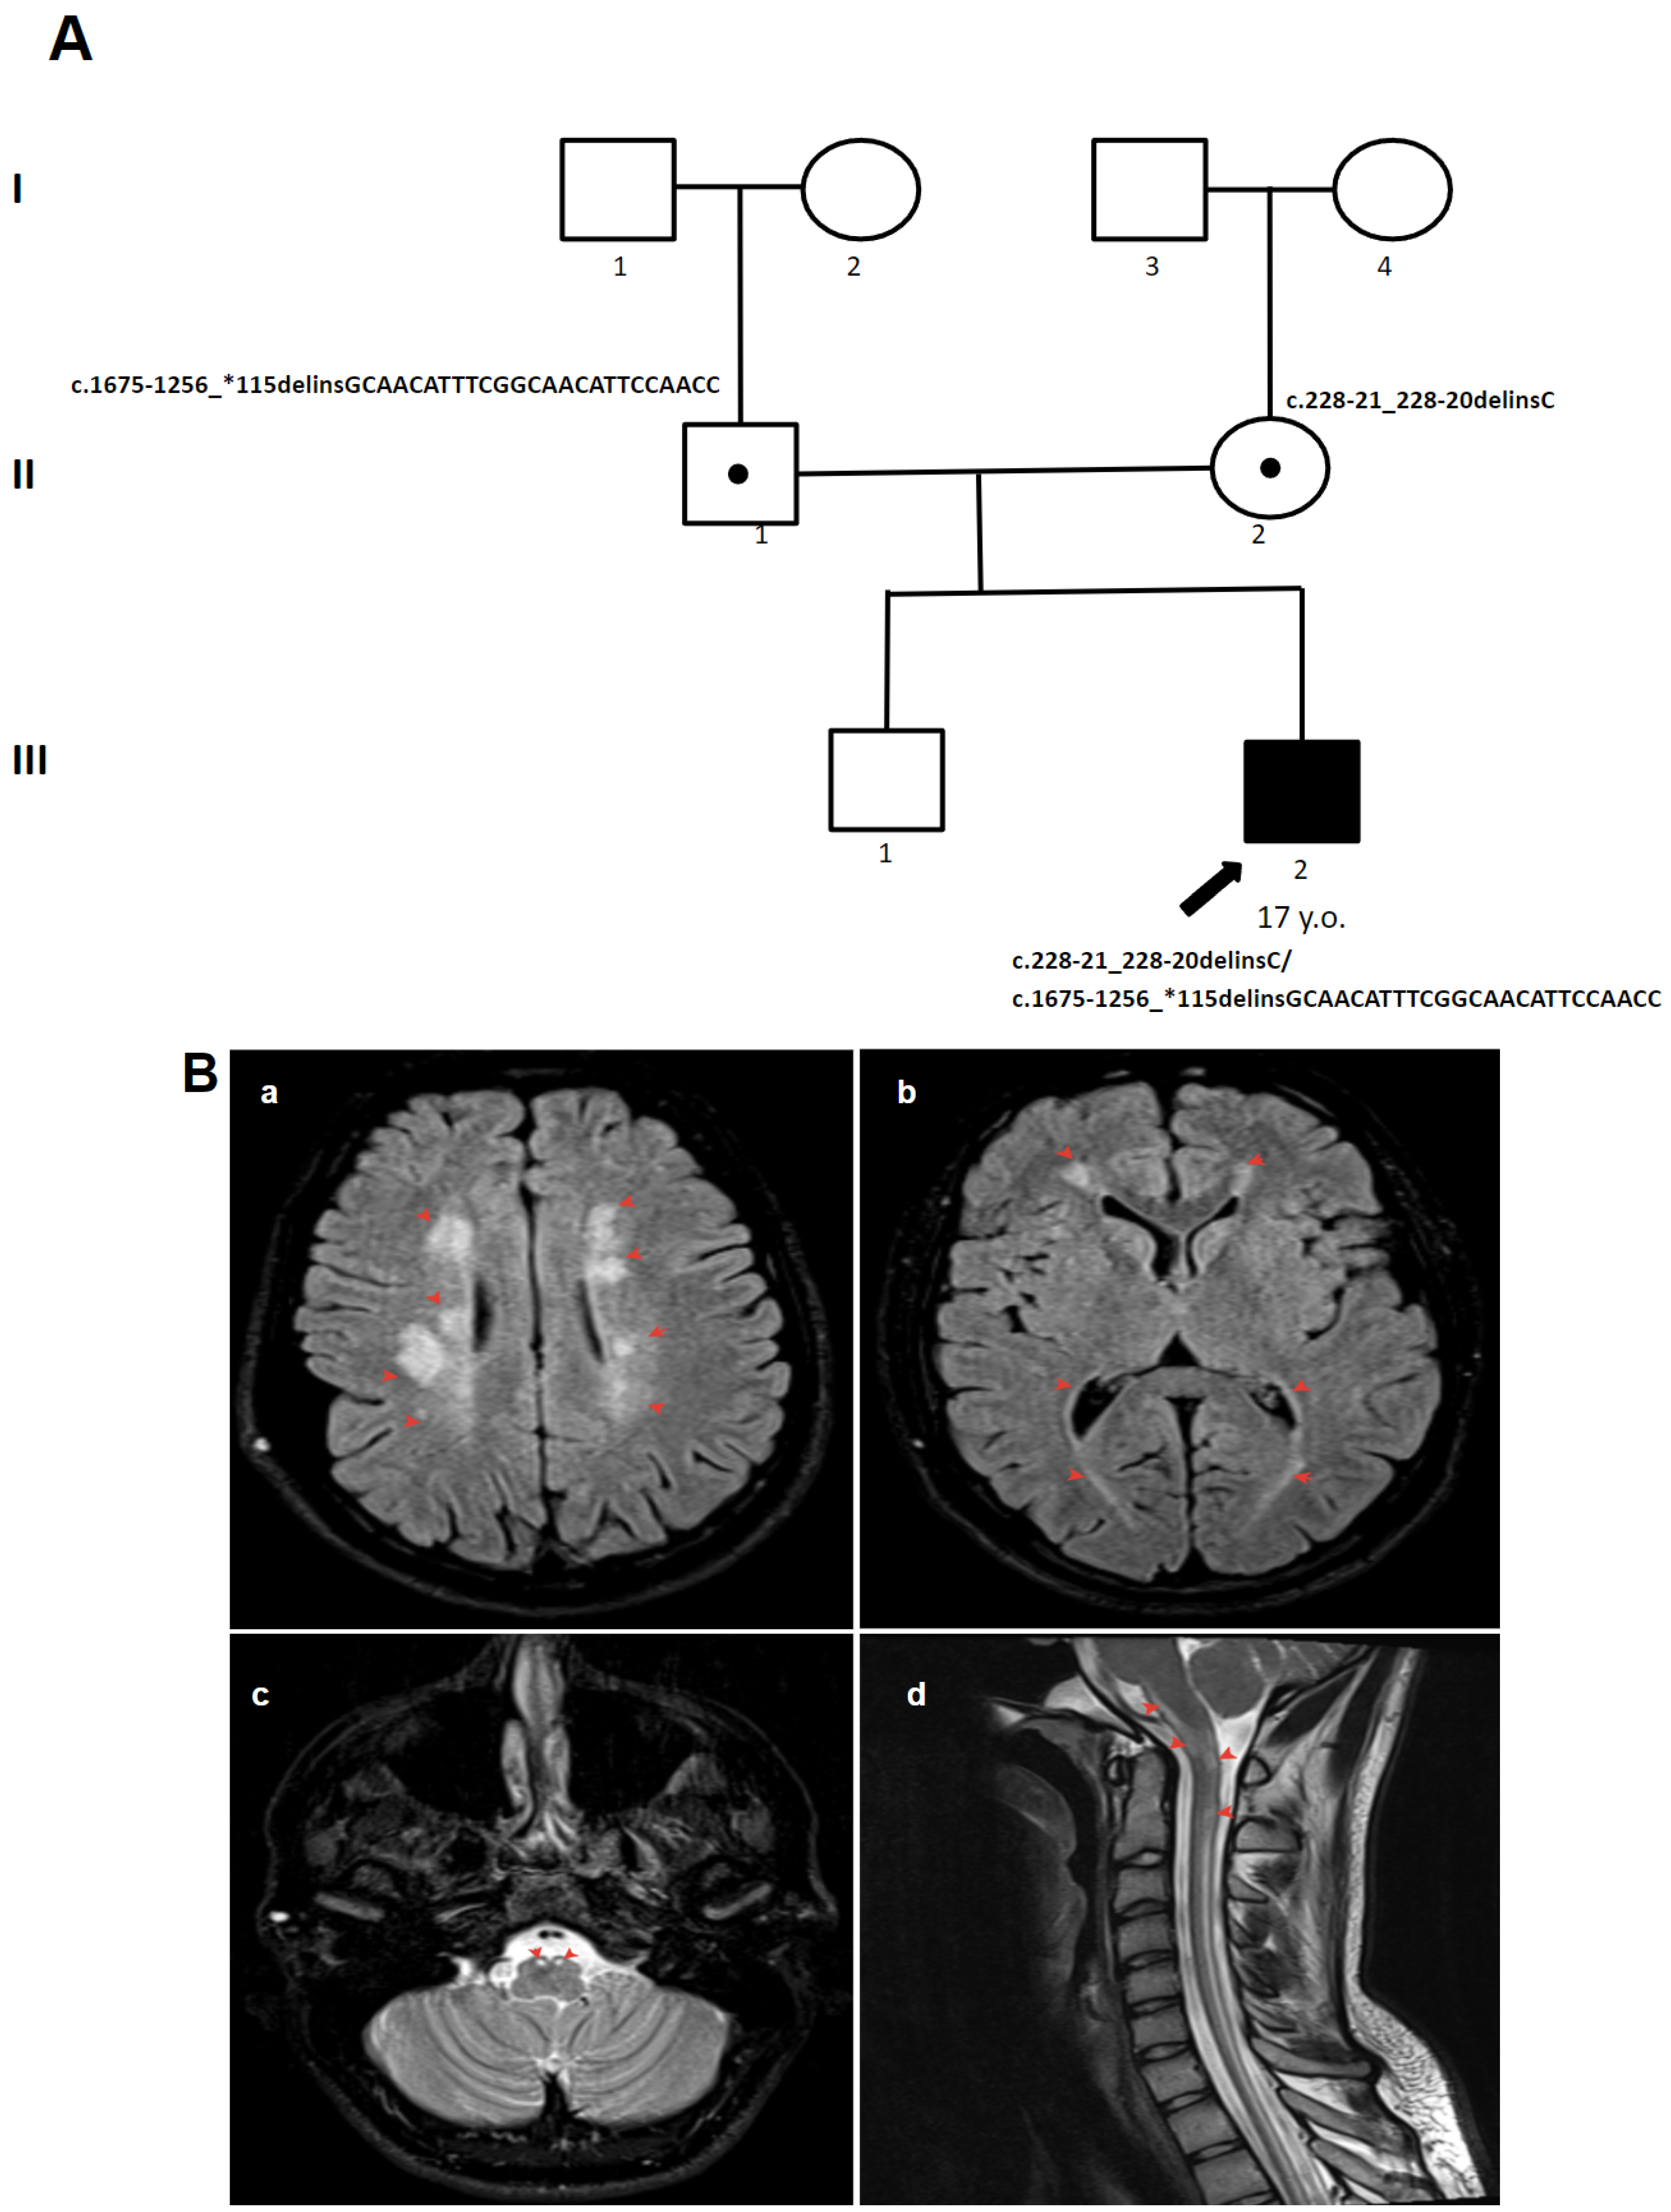

3.1.2. Patient 2

3.2. Molecular Findings